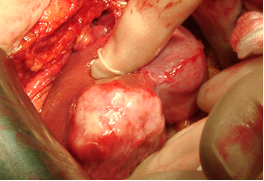

שיטה אחרת לטיפול ב- HCC היא על ידי Radiofrequency ablation (RFA) בשיטה זו משתמשים בגנרטור המייצר גל רדיו בעל תדירות גבוהה מאוד המועברת דרך מחט מיוחדת לשאת וגורמת לחימום השאת והריסתה. את המחט ניתן להחדיר לשאת דרך העור או דרך לפרוסקופ או בראיה ישירה בניתוח פתוח. שאתות מעל 5 ס"מ אינן מתאימות ל- RFA (תמונה 11.10 בהמשך).

בחלק מהחולים ניתן לשלב את טיפול הכריתה עם טיפול הורס של גרורות (ראה טיפולים מקילים). בחולים עם גרורות בודדות באונה השנייה, או בחולים עם סיכון ניתוחי גבוה, ניתן להרוס את הגרורות על ידי אמצעים תרמיים. מצויות היום אלקטרודות מיוחדות שניתן לכוונן למרכז הנגע בכבד ודרכם להעביר אנרגיית חום על ידי חימום או גל רדיו (Radio frequency) או הקפאת השאת ובכך לחסל את גרורה (תמונה 11.10-12.10). בשיטות אלה ניתן להשתמש כאשר קוטר הגרורה קטן (פחות מ- 3 ס"מ) ובחולים עם גרורות בודדות. לעיתים, ניתן לשלב את הכריתה הכירורגית עם הרס תרמי של הגרורות, לדוגמה כריתת אונה מחד גיסא והרס תרמי של הגידול נותר מאידך גיסא.

| תמונה 11.10: RFA . משמאל החדרת המחט לגידול. מימין פתיחת הזרועות דרכן יעברו גלי הרדיו ויהרסו את השאת. | |

|---|---|